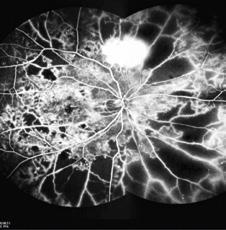

La retina periférica es el sitio de asiento de muchas de las patologías retinales que afectan el fondo de ojos. La examinación cuidadosa a través de la oftalmoscopía con indentación escleral era, hasta hace poco, la única alternativa de visualizar estas estructuras y su documentación se realizaba a través de esquemas del fondo de ojos.

El diagnóstico por imágenes tiene, hoy en día, un papel protagónico en la práctica oftalmológica diaria. La retinografía de campo amplio (UWF) cambió la forma de evaluar y documentar el fondo de ojos de los pacientes. A diferencia de la oftalmoscopía, este estudio brinda la posibilidad de observar y documentar en diferentes modalidades los hallazgos de las estructuras del fondo de ojos en su totalidad como por ejemplo color, red free y FAF (autofluorescencia). Esto mismo sucede con las angiografías de fondo de ojos con fluoresceína e indocianina verde, que permiten evaluar la presencia de isquemia y vasculitis en regiones antes inaccesibles para este tipo de estudios.

Astatec SA, representante de Zeiss en Argentina, consultó al doctor Rodrigo Santos, especialista en Retina , sobre su

experiencia con Zeiss Clarus 700-500: cámara retinal de campo ultra amplio que captura imágenes desde la mácula hasta la periferia lejana que permite ver indicios sutiles de distintas enfermedades en cualquier parte de la retina.

¿Qué destacaría del Zeiss Clarus?

El Clarus 700 permite la toma de 130 grados de retina en una sola foto y 200 grados con

dos tomas, con una excepcional claridad gracias a su sistema de enfoque que mantiene en foco la totalidad de la retina. Por otra parte, construye una imagen con colores reales, facilitando la identificación de lesiones. Genera a su vez menos deformación de la imagen brindándonos una imagen similar a la observación con el oftalmoscopio. Su software permite descomponer la imagen en sus diferentes filtros, a la vez que captura en modo autofluorescencia y angiografía.

La retinografía de campo amplio es hoy una herramienta indispensable para el screening y documentación del estado del fondo de ojos. Agiliza mi flujo de trabajo al tener la imagen de fondo de ojos en mi pantalla antes del ingreso del paciente a la consulta y me permite controlar la evolución al comparar con imágenes previas. Como herramienta diagnóstica, la angiografía de campo amplio ha cambiado nuestro enfoque del diagnóstico, valoración del daño e indicación de tratamiento en las vasculopatías de todo tipo. Por último, considero que es una herramienta educativa de gran valor, tanto para pacientes como para médicos en formación.